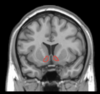

Wada test

Can be used to demonstrate hemispheric dominance.

Injection of sodium amytal into the ICA.

On the dominant side this will cause an arrest of speech for up to 30 seconds.

May be useful prior to temporal lobectomy when there is doubt over hemispheric dominance